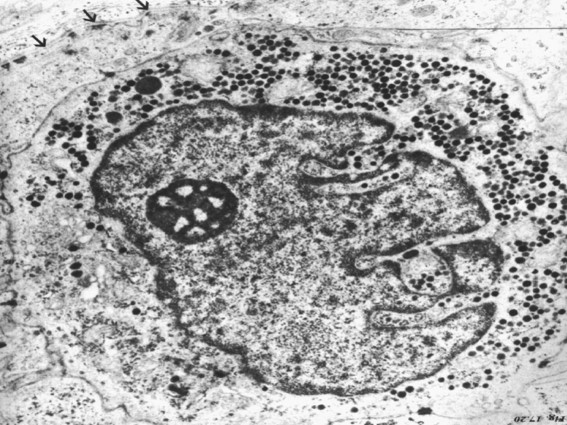

2.朗格汉斯细胞(Langerhans cell):一种有树枝状突起的细胞。主要位于棘层。来自于造血组织,作为抗原呈递细胞,可以激活T淋巴细胞。电镜下在胞质中有特殊的棒状或球拍样颗粒(图5.1-8)。

图5.1-8 朗格汉斯细胞